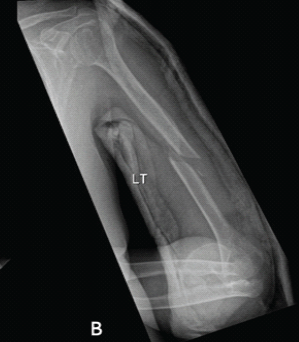

Aneurysmal Bone Cyst Presenting as a Pathological Subtrochanteric Femur Fracture in an Adolescent: A Case Report

Chandrashekhar R Rai , Sandeep V Gavhale , Vijaysing Chandele , Alok P Yadav , Chinmay S Torne , Vishal B Karpe